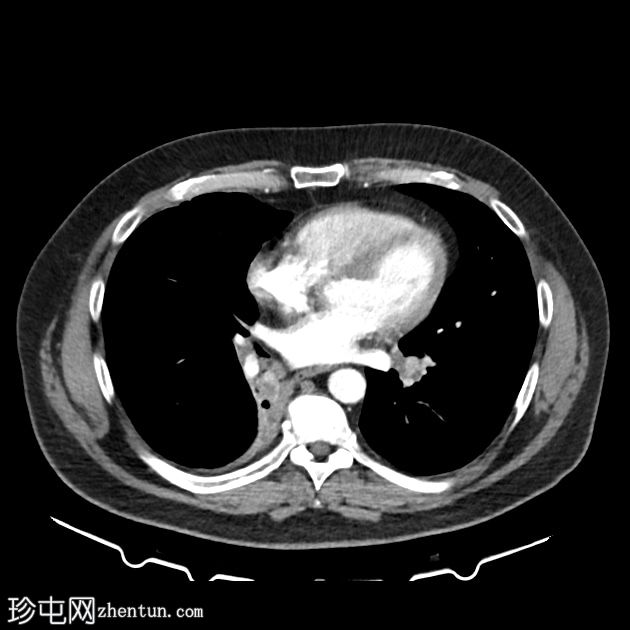

轴位增强扫描

动脉期

右下肺支气管内肿块较前增大,现已延伸至中间支气管,并可见对比剂强化。右下肺阻塞性肺不张。

左下肺支气管出现新的类似肿块。